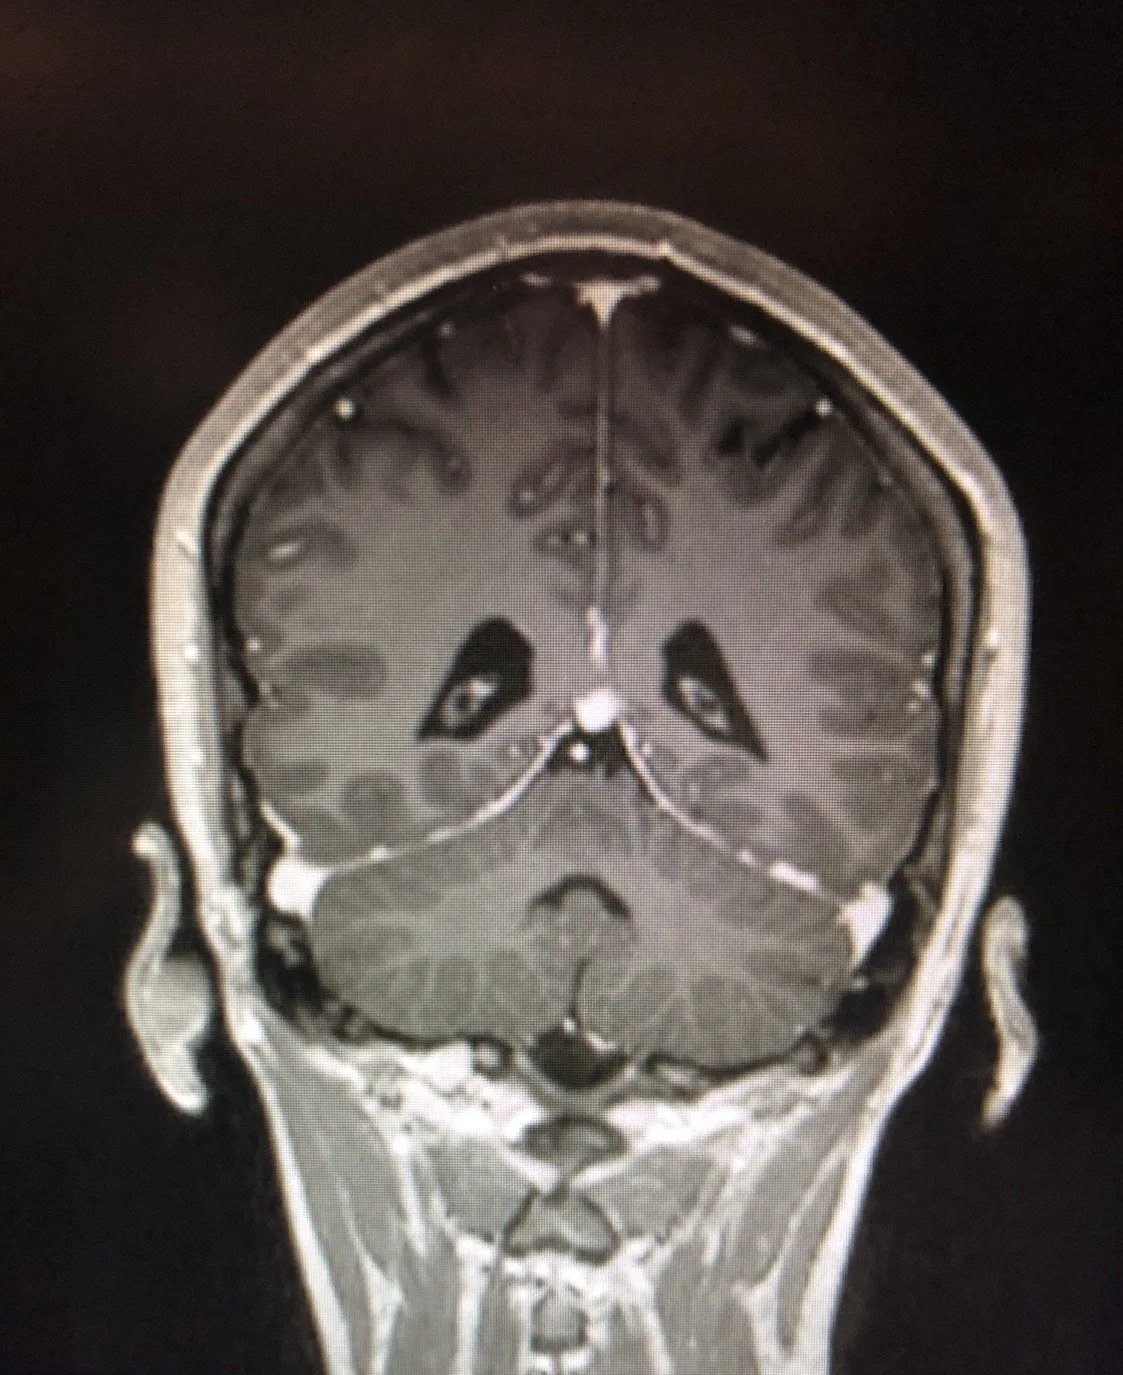

I made this piece using my own MRI scans that still crack me up to this day (swipe to see). Last year after some testing, I noticed this one image which looks like a sad little man in my brain. I blame him for my depression lmao. At least he’s cute. Sad Brains is my play on Bad Brains, who helped pioneer hardcore punk…something that also helps during these unhinged moments.